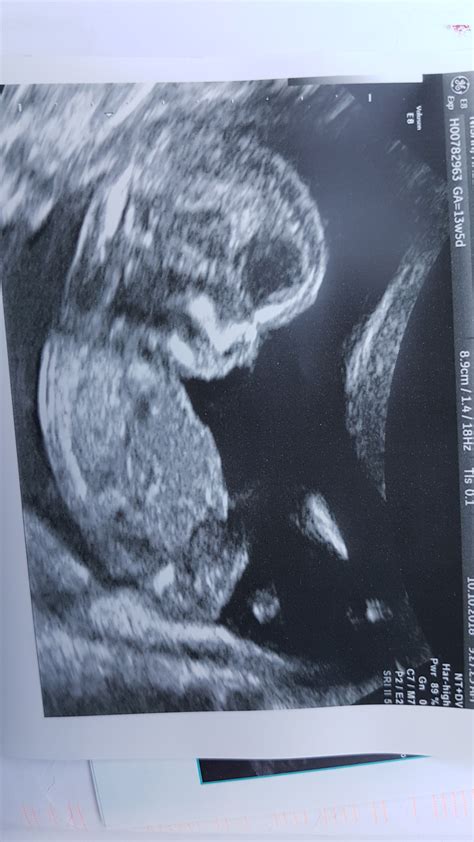

Pregnancy is an exciting journey filled with milestones, and one of the most anticipated moments is the 13 Weeks Ultrasound. This scan, typically performed between 12 and 13 weeks of gestation, offers a wealth of information about the developing fetus and the mother's health. Understanding what to expect during this ultrasound can help alleviate anxiety and prepare expectant parents for the next steps in their pregnancy journey.

A 13 Weeks Ultrasound is a routine prenatal check-up that uses high-frequency sound waves to create images of the fetus and the uterus. This scan is crucial for several reasons, including assessing the fetus's development, detecting any potential issues, and providing a clearer picture of the pregnancy timeline.

• Fetal Development Assessment: At 13 weeks, the fetus undergoes significant developmental changes. The ultrasound can confirm the fetus's age, measure the crown-rump length (CRL), and check for the presence of key structures like the heart, brain, and limbs.

• Visual Confirmation: Seeing the fetus on the ultrasound screen can be an emotional and reassuring experience. At this stage, the fetus is about the size of a plum, and its features are becoming more distinct.

• Crown-Rump Length (CRL): This measurement helps determine the fetus's gestational age and overall growth.

• Fetal Anatomy: The ultrasound will check for the presence of key structures, such as the heart, brain, and limbs, to ensure normal development.

• Placenta and Uterus: The position of the placenta and the condition of the uterus will be evaluated to ensure everything is progressing normally.